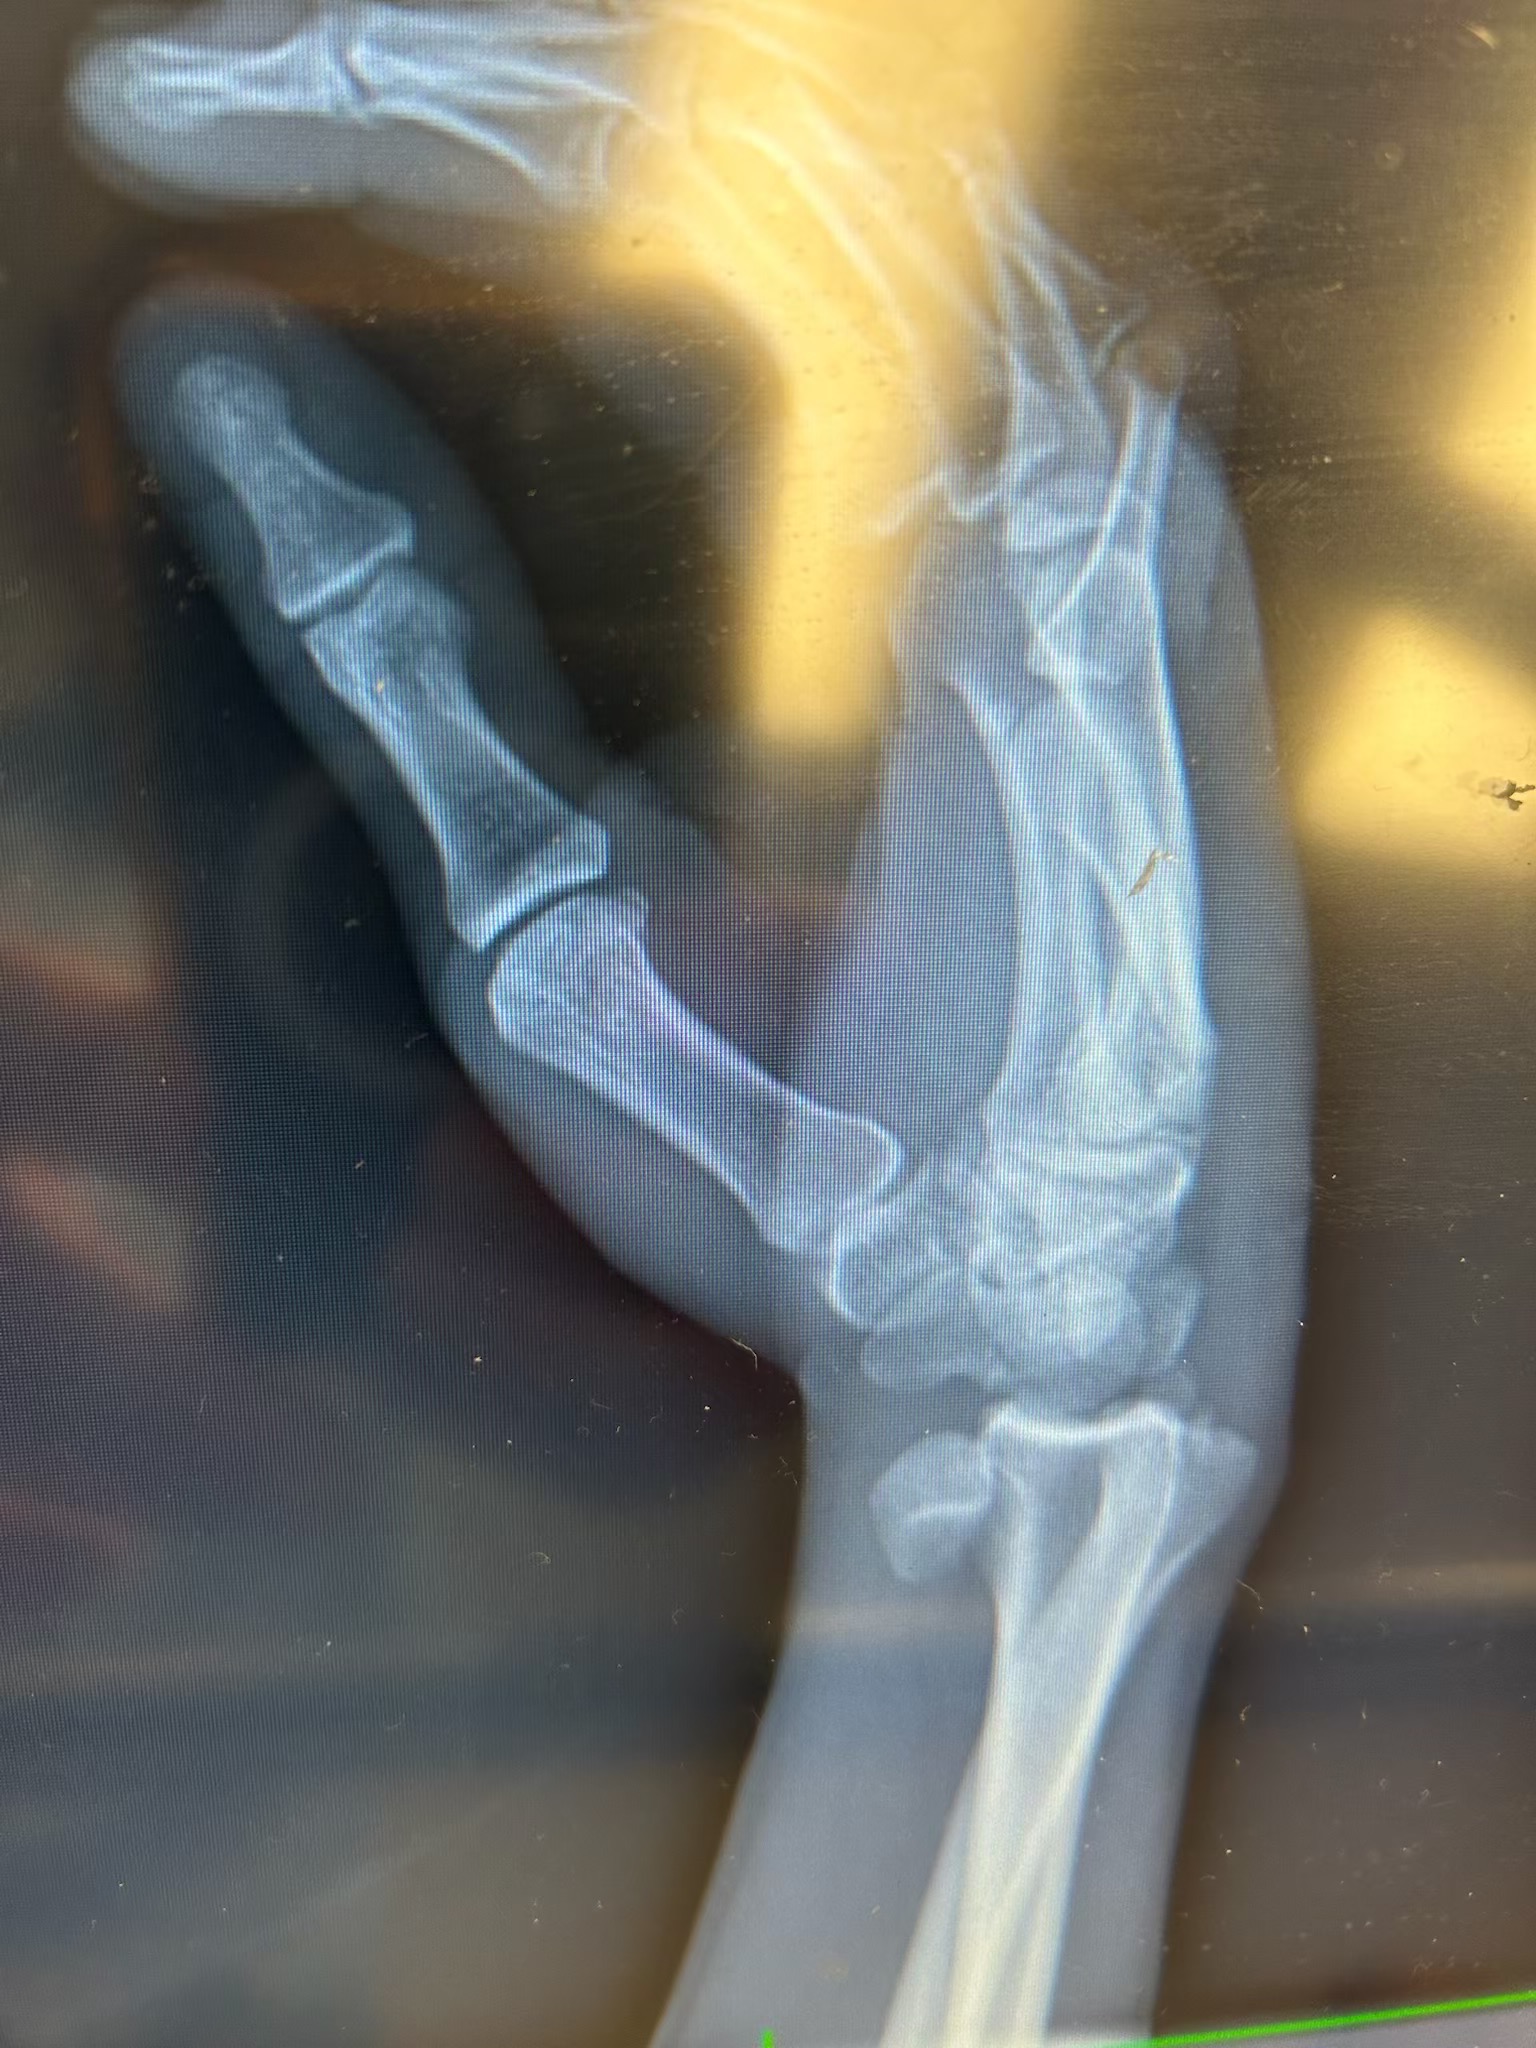

I’m helping to raise funds for Andy who was in a horrific motorcycle accident on 8/24. He has a long road of recovery ahead of him. His medical expenses are going to be huge, with ICU care, surgeries, rehabilitation, and prosthetics for his leg. He is a father of 2 young children who now has no income, and insurance will only cover so much. He’s looking at many months of care beyond just family care to help with, and no income to help cover costs. He’s dealing with the loss of his leg, surgery tomorrow on his hands and wrists, another surgery Friday for his right shoulder, and no date yet for his surgery for his right foot. Any donation would be greatly appreciated to help cover medical costs and monthly bills till he can return to work.

He had his surgery today on both hands and his right foot, went well. Lots of pins and some screws. He still has 1 more surgery scheduled for Friday on his scapulae on right side waiting for special plate to secure and fix.